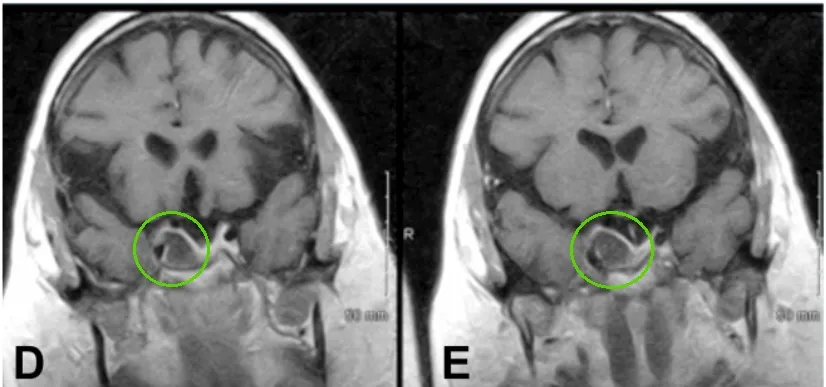

第二次手术后MRI,显示肿瘤残余,继发性空蝶鞍综合征伴有鞍区前交通动脉复合体的下移位。

在法国巴黎的Lariboisiere大学医院,福洛里希教授制定了治疗方案。“第一步是经鼻内镜入路行视交叉“固定”术。第二步需切除肿瘤,并重建鞍底。防止肿瘤复发的同时,缓解目前视力下降的困境。”

术后一年,MRI显示肿瘤全切、脂肪填充空蝶鞍。术后左侧视野改善,视力稳定在0.3.右侧视力从0.03改善到1.0、如正常视力。

术后一年MRI